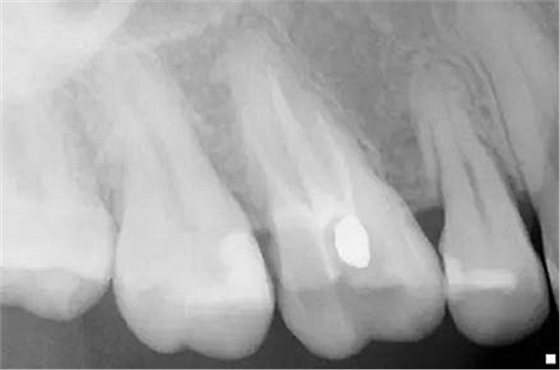

步驟2

原始x線影像

X線攝片狀況。